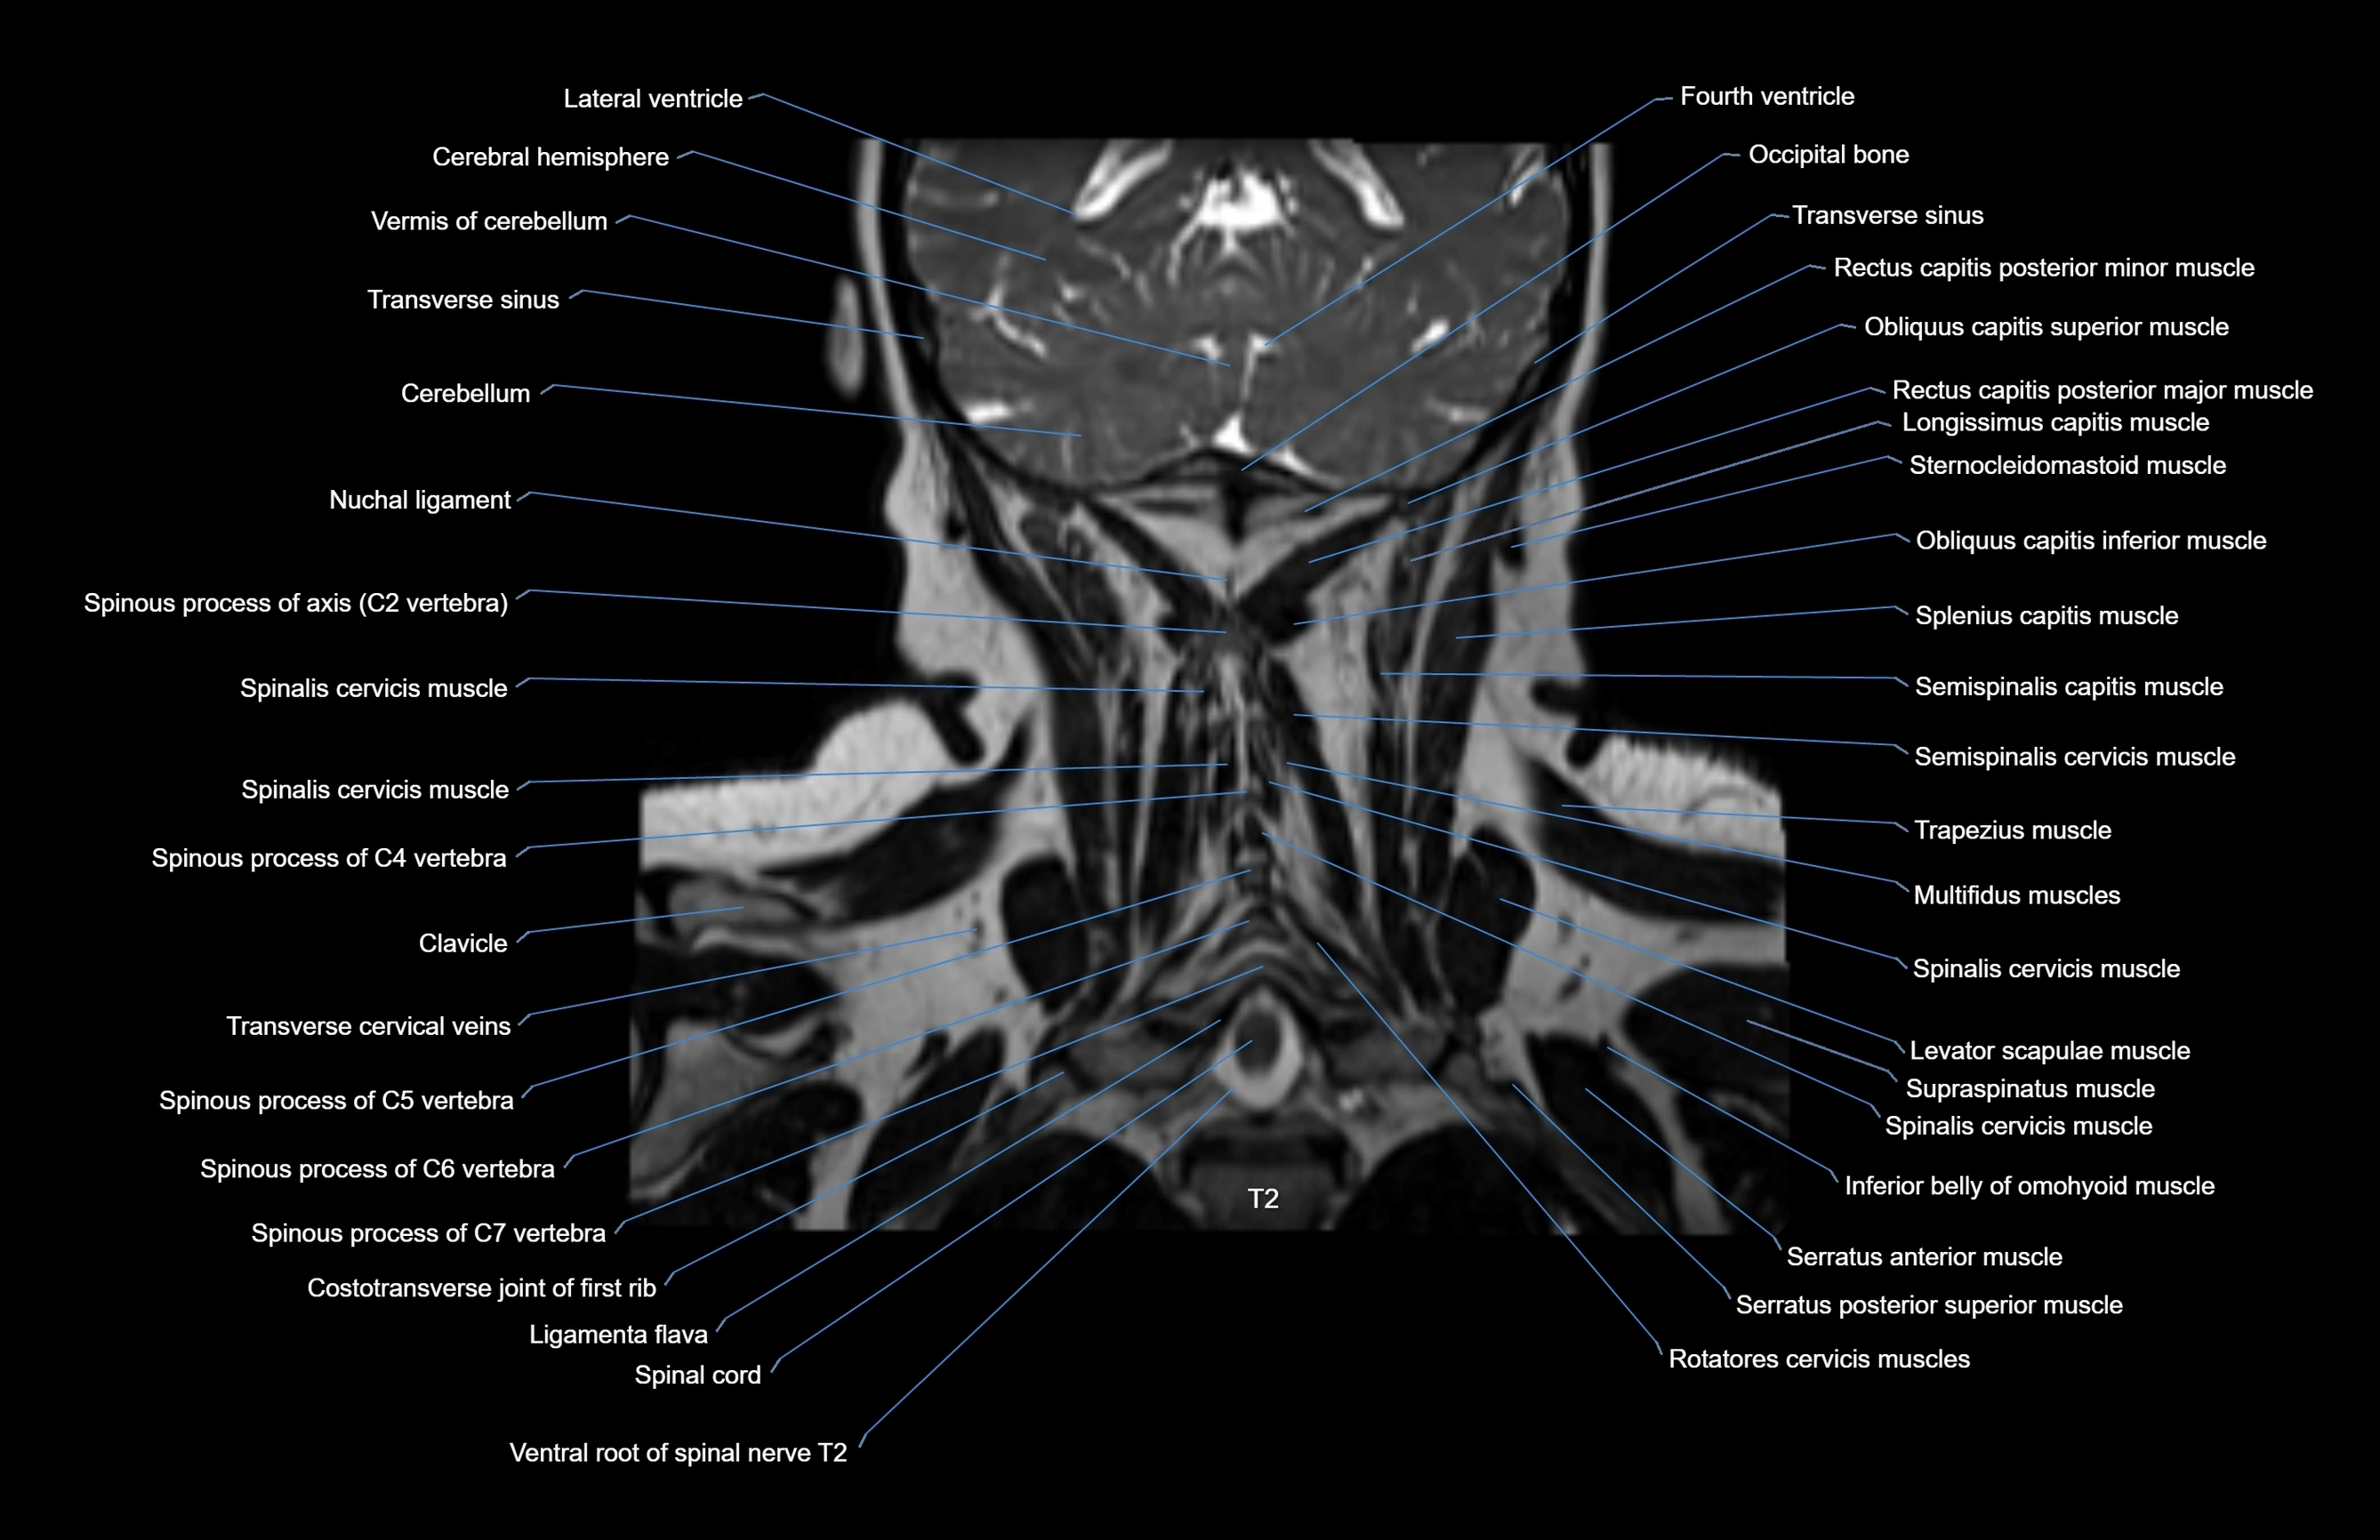

MRI images